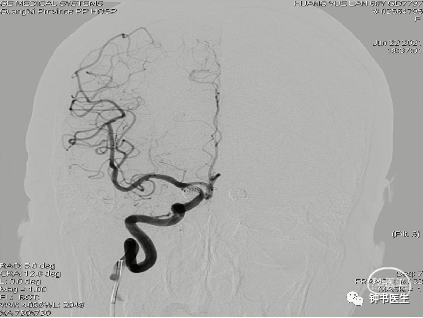

2021-06-22 DSA

R-ICA